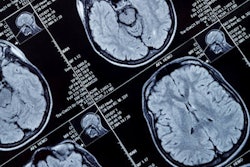

The integrity of the white matter is impaired with higher body mass index (BMI) scores in children, researchers found. The most affected areas include the corpus callosum, which is the main connector of both brain hemispheres, and the superior longitudinal fasciculus that connects several lobes. Images and caption courtesy of the RSNA.Kaltenhauser and colleagues found that higher weight and BMI scores were linked to lower fractional anisotropy values, lower axial diffusivity values, and lower neurite density values, among other values with tracts within the brain's hemispheres that connect the lobes.

For both weight and BMI scores, fractional anisotropy reductions were most pronounced in the corpus callosum, fornix, and (parietal and temporal) superior longitudinal fasciculus regions of the brain. The corpus callosum is the primary connector between the brain's two hemispheres.